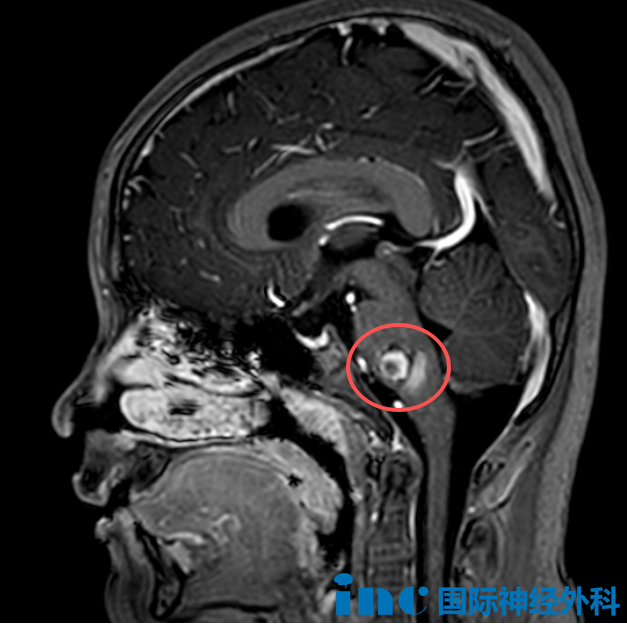

與此同時(shí),9歲的菲律賓男孩達(dá)恩也在面對(duì)另一重挑戰(zhàn)——他的腦干深處生長(zhǎng)著一處16×11×14mm的“爆米花”樣病變。面對(duì)這個(gè)被稱為“手術(shù)禁區(qū)”的挑戰(zhàn),達(dá)恩的家人在了解到巴教授在腦干手術(shù)領(lǐng)域的深厚經(jīng)驗(yàn)后,毅然跨越國(guó)界,只為給孩子爭(zhēng)取一個(gè)手術(shù)的機(jī)會(huì)。術(shù)前談話時(shí),巴教授詳細(xì)分享了手術(shù)的具體操作,包括手術(shù)體位、手術(shù)入路、術(shù)中監(jiān)測(cè)等。一切努力都指向同一個(gè)目標(biāo):在保障安全的前提下最大程度切除病灶,同時(shí)保護(hù)神經(jīng)功能。達(dá)恩的家長(zhǎng)反復(fù)表達(dá)對(duì)巴教授“神奇之手”的信任,他們相信,這位國(guó)際大咖能為更多患兒點(diǎn)亮希望。

影像